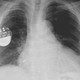

A key drawback of most wearable and implantable devices still remains their batteries, whose limited capacities restrict their long-term use. The last thing you want to do when, say, a pacemaker runs out of power is to open up a patient just for a battery replacement. The solution to this problem may rest inside the human body—rich as it is in energy, in its chemical, thermal, and mechanical forms. This has led scientists to investigate a plethora of ways for devices to harvest energy from the bodies that host them, detailed by Dagdeviren and her colleagues in the 2017 Annual Review of Biomedical Engineering.

So far, such devices have been tested in cows, sheep and pigs, all animals with hearts roughly the same size as those of people. “When these devices mechanically distort, they create positive and negative charges, voltage and current—and you can collect this energy to recharge batteries,” Dagdeviren explains. “You can use them to run biomedical devices like cardiac pacemakers instead of changing them every six or seven years when their batteries are depleted.”